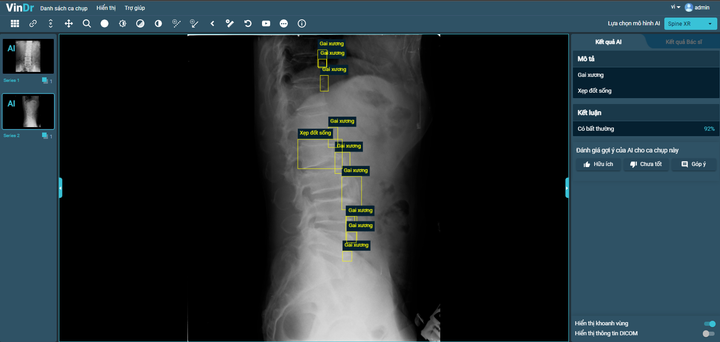

Sau hơn 1 năm tiếp tục nghiên cứu và phát triển, VinBigdata đã tiếp tục phát triển thành công tính năng chẩn đoán X-quang cột sống, phát hiện 6 loại tổn thương phổ biến tại Việt Nam, bao gồm: gai xương; hẹp khe đĩa đệm; vật liệu phẫu thuật; hẹp lỗ tiếp hợp; trượt đốt sống và xẹp đốt sống với độ chính xác khoảng 90%.

VinDr hoàn thiện tính năng mới SpineXR, hỗ trợ chẩn đoán ảnh X-quang cột sống với độ chính xác khoảng 90%.